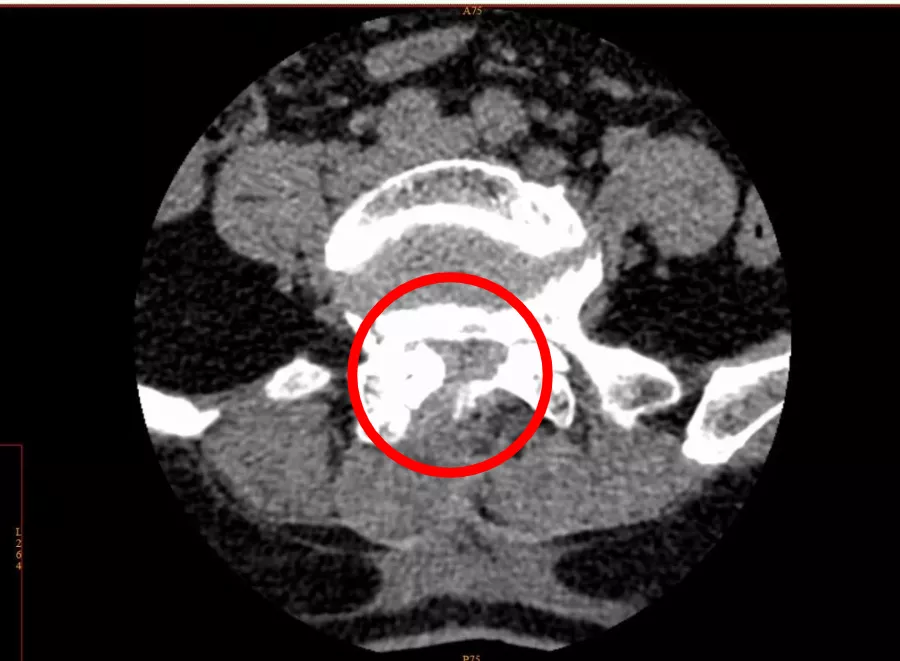

通过CT影像报告,疼痛科主任肖林发现了问题所在——腰椎管狭窄。

CT影像显示,李女士的腰椎管存在狭窄

术后,腰椎管狭窄改善